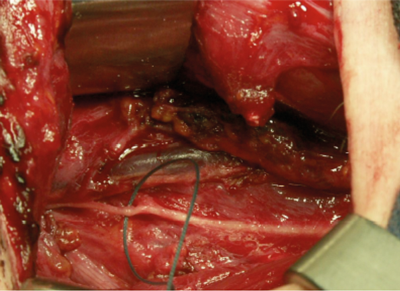

Figure 3. Upper root of phrenic nerve identified and to be ligated to provide inspiratory firing to the PCA muscles.

The technique involves utilising the upper root of the phrenic nerve on one side (Figure 3) to provide inspiratory innervation to both posterior cricoarytenoid (PCA) muscles via a Y-shaped cable graft. Phonatory closure is achieved by using the nerve to the thyroid hyoid muscle to supply motor fibres to the distal stump of the recurrent laryngeal nerve (via an interposition graft) bilaterally. These fibres are not active on respiration and so do not counteract the effect of the phrenic fibres now responsible for inspiratory contraction of the PCAs (Figure 4).